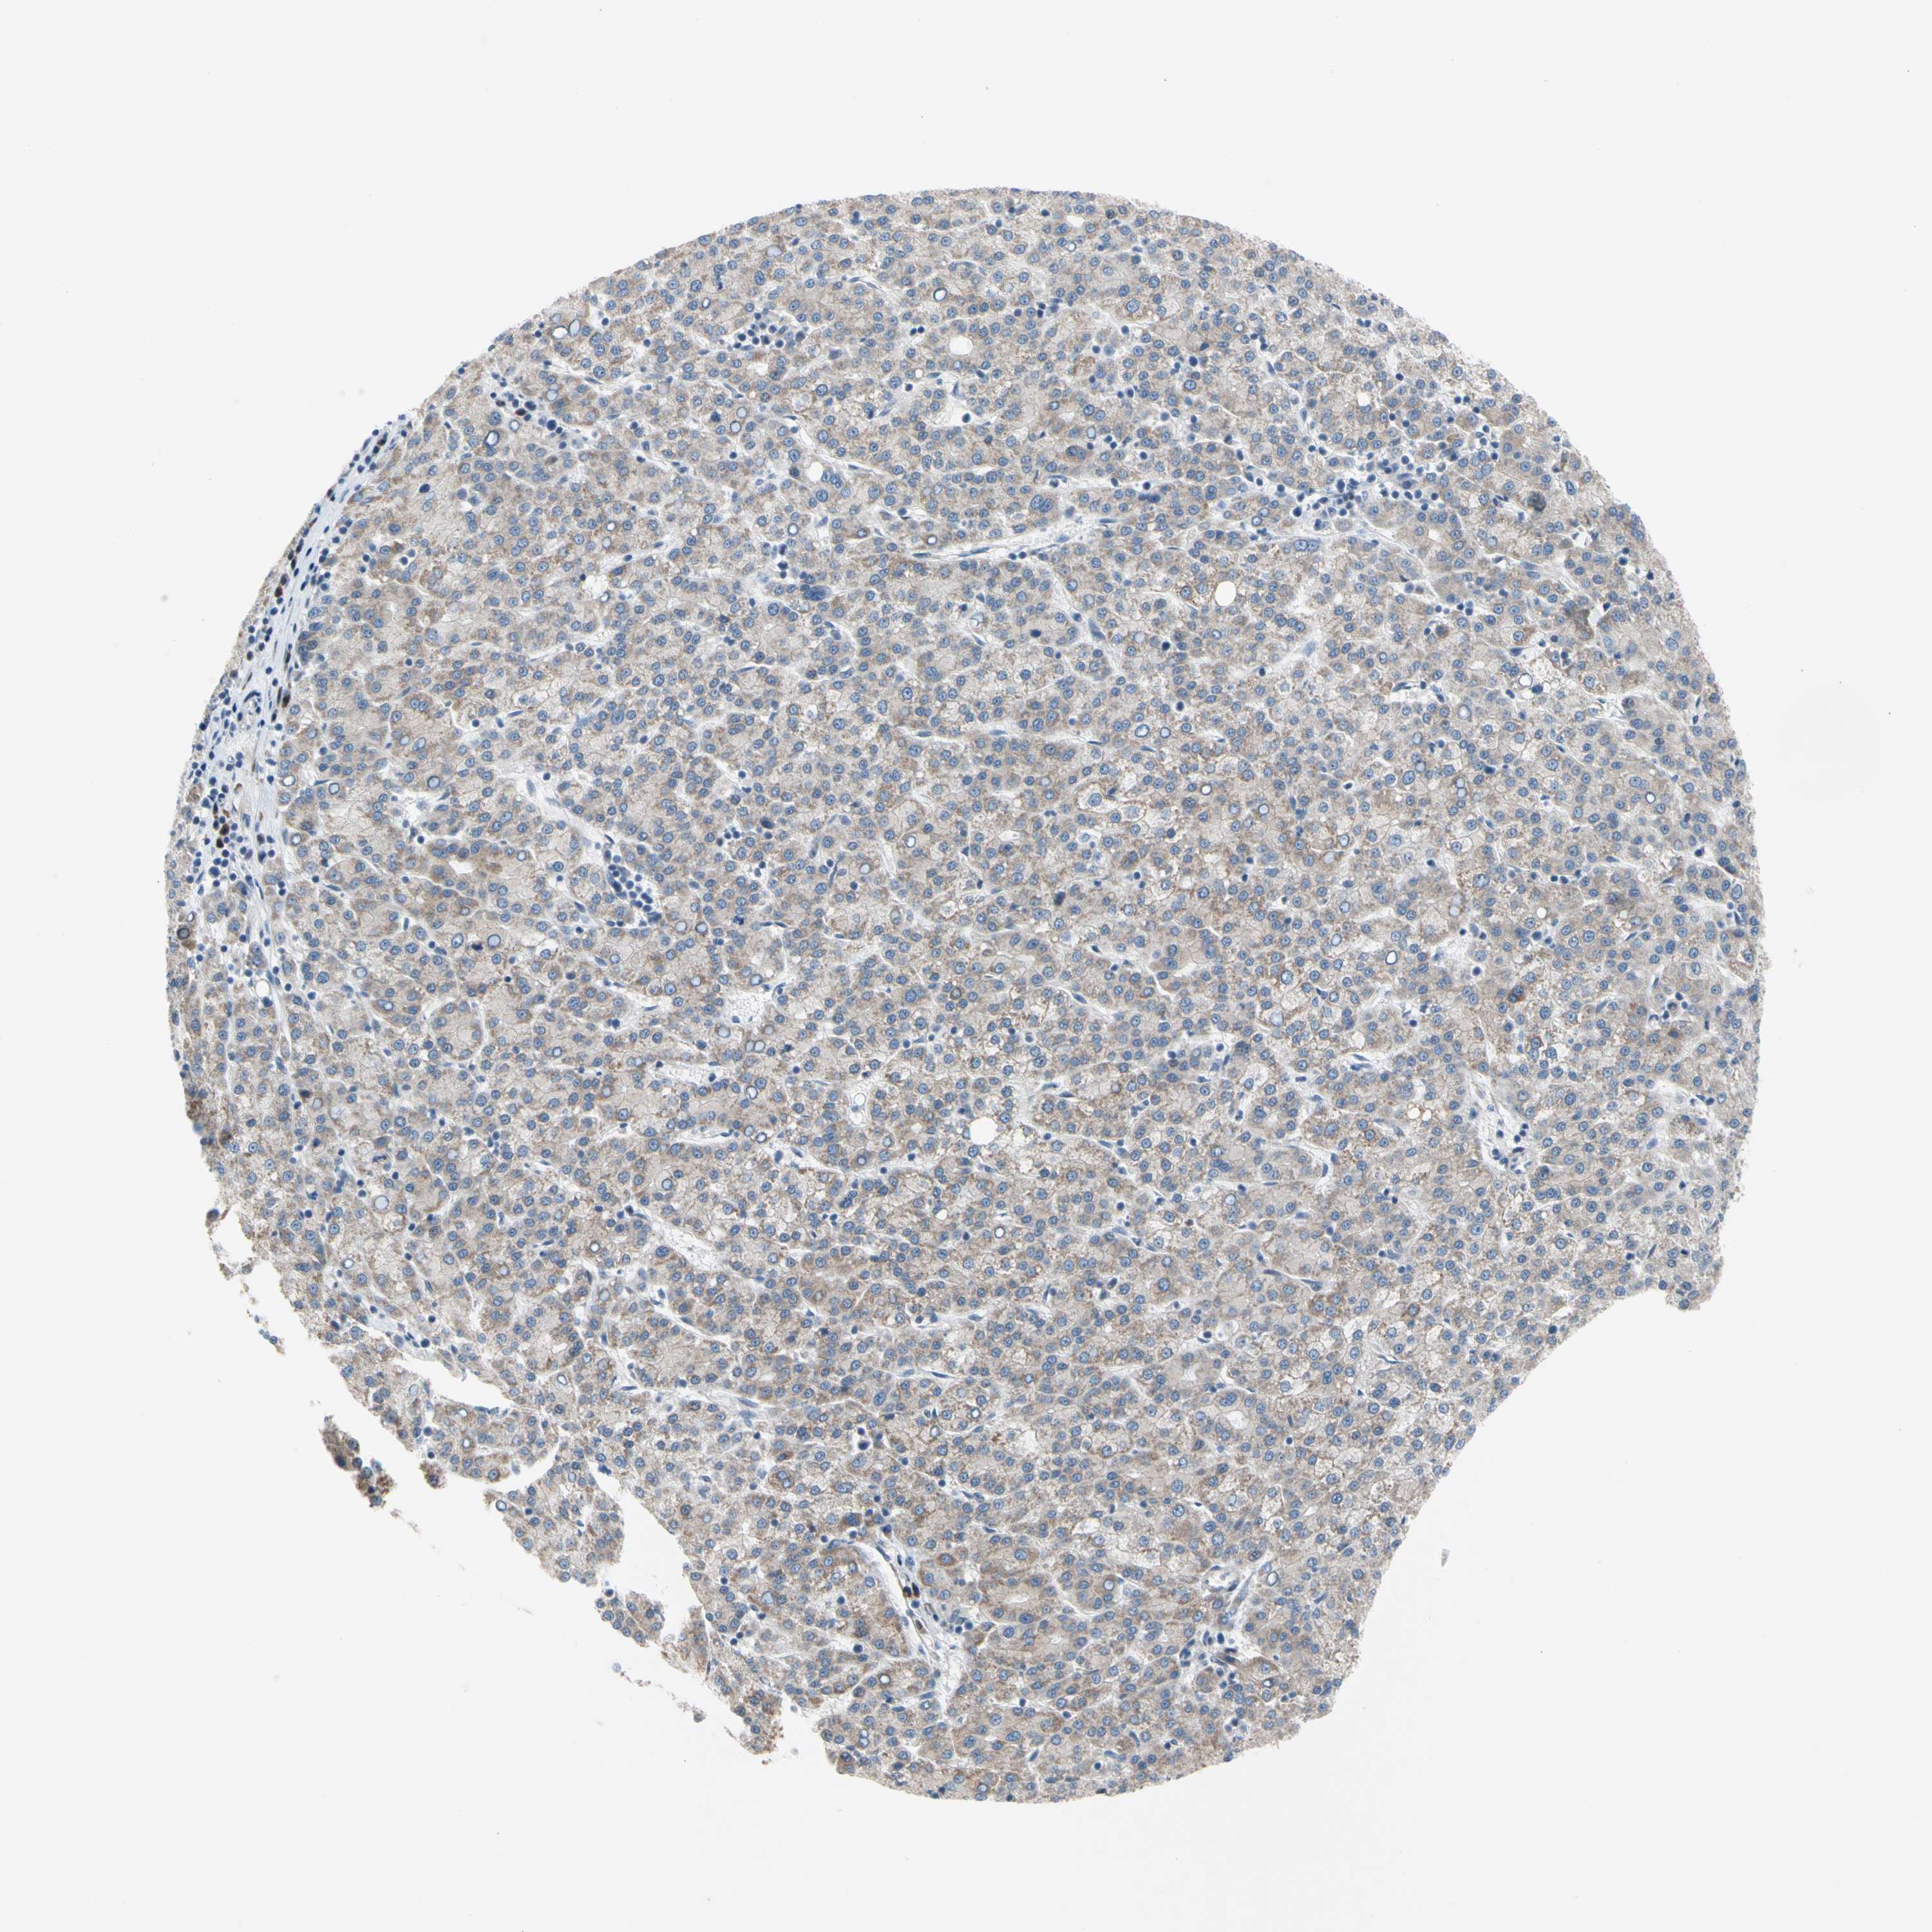

LIVER CANCER - Protein expressioni

A mouse-over function shows sample information and annotation data. Click on an image to view it in a full screen mode. Samples can be filtered based on level of antibody staining by selecting one or several of the following categories: high, medium, low and not detected. The assay and annotation is described here.

Note that samples used for immunohistochemistry by the Human Protein Atlas do not correspond to samples in the TCGA dataset.

Antibody stainingi

Antibody staining in the annotated cell types in the current human tissue is reported as not detected, low, medium, or high, based on conventional immunohistochemistry profiling in selected tissues. This score is based on the combination of the staining intensity and fraction of stained cells.

Each image is clickable and will lead to virtual microscopy that enables deeper exploration of all samples and also displays staining intensity scores, fraction scores and subcellular localization as well as patient and tissue information for each sample.

Antibody HPA007421

Antibody HPA008061

Staining

High

Medium

Low

Not detected

Intensity

Strong

Moderate

Weak

Negative

Quantity

>75%

75%-25%

<25%

None

Location

Nuclear

Cytoplasmic/membranous

Cytoplasmic/membranous,nuclear

Cholangiocarcinoma

Carcinoma, Hepatocellular, NOS